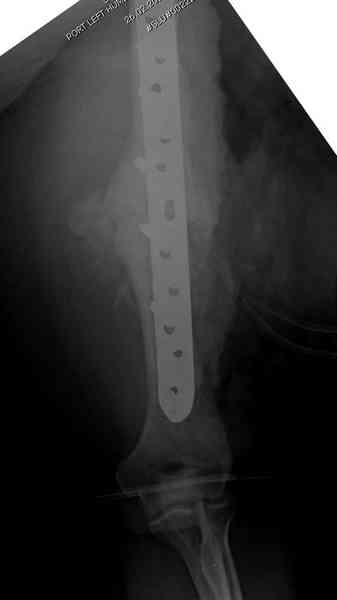

Как видно из выступлений коллег, способы фиксации

ложного сустава плеча могут быть различными, кто-то предпочитает аппаратом Илизарова (Соломин), пластинами (Волна) или интрамедуллярным гвоздем (Челноков).

Когда разбирался случай на сайте, и у нас была больная с похожей патологией, ложный сустав после поперечного перелома, леченного год назад где-то и кем-то в другом месте.

Первичную пластину убрали недели 6 назад из переднего оригинального доступа, и из-за подозрительности тканей вокруг пластины, решили провести реконструкцию поэтапно.

Хотя сам не стороннник применения более массивных

имплантов для плеча, но для этого случая сделали

исключение. На снимке 4А диаметр мягких ткани около 20 см, при весе больной более 135 кг, и также выступление Андрея Волны подстегнуло к применению более массивной 4.5 мм локинг пластины.